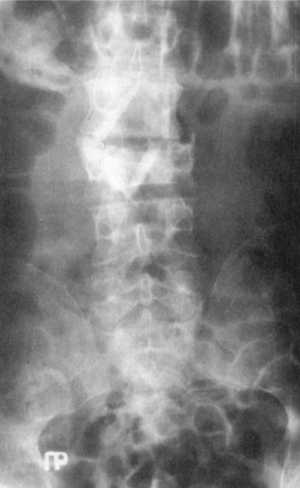

Рис. 12.7. Рентгенограмма после хирургического

вмешательства при повреждении L3-позвонка (прямая проекция) |

При осложненной травме позвоночника с корешковыми неврологическими расстройствами,

производится лишь резекция поперечных отростков с обеих сторон на уровне поврежденного

позвонка, через корни дуг выполняются каналы в телах выше- и нижерасположенных

позвонков и вводятся костные кортикальные аллотрансплантаты. При необходимости

операцию можно дополнить задним спондилодезом костными аллотрансплантатами

(рис. 12.7).